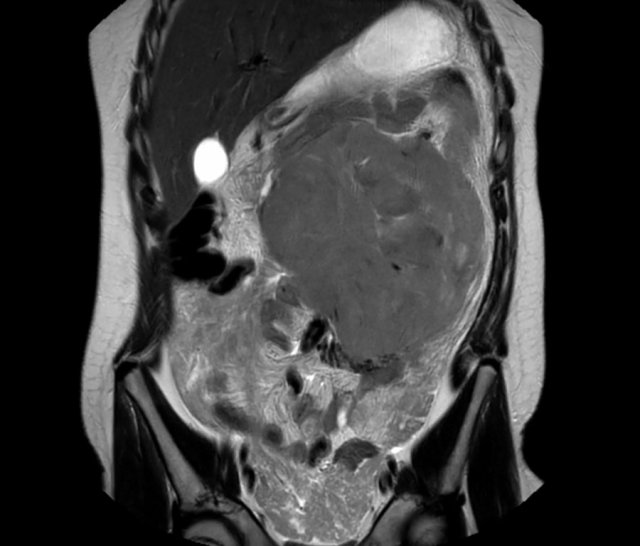

Nephroblastoma of the left kidney in a three-year-old boy. The remnant of the kidney is draped over the tumor (“claw sign” arrow). The tumor is rather homogeneous with some cystic areas.

Continue with the MRI.